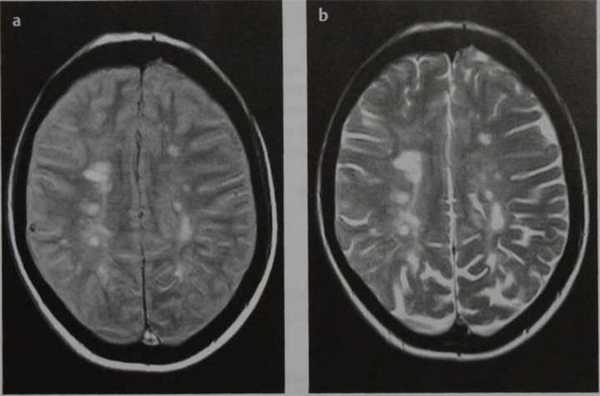

Рассеянный склероз. МРТ, взвешенное по протонной плотности изображение (а) и Т2-ВИ (b) в аксиальной плоскости. Гиперинтенсивные очаги в перивентрикулярном белом веществе.